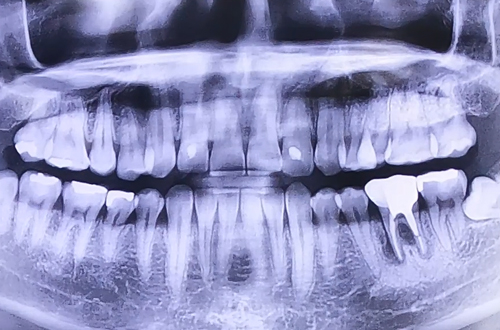

BEFORE

치료 유형 뼈이식 임플란트